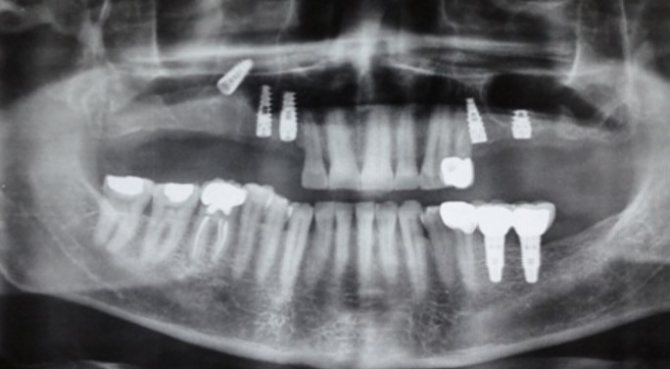

- В процессе установки импланта в кость верхней челюсти с последующим протезированием зуба может быть легко повреждена гайморова полость. Это происходит потому, что имплант похож на шуруп и должен быть ввинчен в кость. При дефектах проведения этой манипуляции или анатомо-топографических особенностях у больного может быть повреждена костная пластинка верхней челюсти (неправильно подобран размер импланта, были дефекты подготовки к имплантированию). Врач не учитывает перед постановкой импланта то, что при удалении зуба толщина костной пластинки быстро уменьшается.

Если процесс происходит в момент внедрения импланта в костную ткань или при пломбировании каналов, то это прямая ошибка, которая совершается врачом во время его терапевтической тактики. Единственным способом контролирования манипуляций является рентгенологический контроль и опыт стоматолога, который при работе должен учитывать анатомическое строение верхней челюсти пациента. При этом повреждения дна пазухи чревато серьезными осложнениями, которые сложно устранить. Особенно если это происходит во время имплантации искусственных корней. Костная ткань в области верхней челюсти быстро подвергается дистрофическим изменениям, и это ведет к уменьшению высоты альвеолярного отростка.

При проникновении в гайморову пазуху инородных тел при перфорации (обломки корней зуба, пломбировочные материалы, прободение импланта) лечение проводится в стационарных условиях. В тяжелых случаях могут проводиться оперативные вмешательства на гайморовой пазухе с ее дальнейшим вскрытием, при котором проводится очищение тканей и удаление инородных тел. После санации делается пластическое закрытие образовавшейся перфорации.

Если перфорация осложнена разрывом десны и пенетрацией инородных частиц в мягкие ткани, окружающие лунку зуба, выполняют пластическое закрытие дефекта в этот же день. Или через некоторое время, когда будет уверенность, что ткани будут держать швы. Перед этим удаляют все инородные тела и иссекают участки, подвергшиеся некрозу. Манипуляцию выполняют под рентген контролем, чтобы удостовериться, что там нет инородного тела. Если произошло проникновение в полость инородного тела, то необходимо делать операцию в условиях стационара.

Этапы операции:

- Вскрытие основной пазухи верхней челюсти.

- Удаление зуба из гайморовой пазухи (его обломков) и иных инородных тел.

- Иссечение некротических участков.

- Закрытие дефекта.